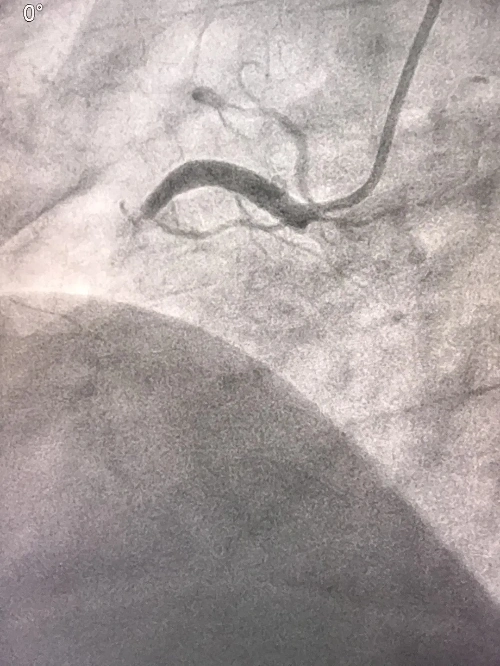

77岁老人急性下壁心肌梗死,博医心内科紧急pci挽救患者生命!